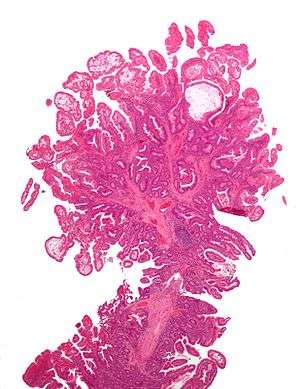

Microvesicular hyperplastic polyp. H&E stain.